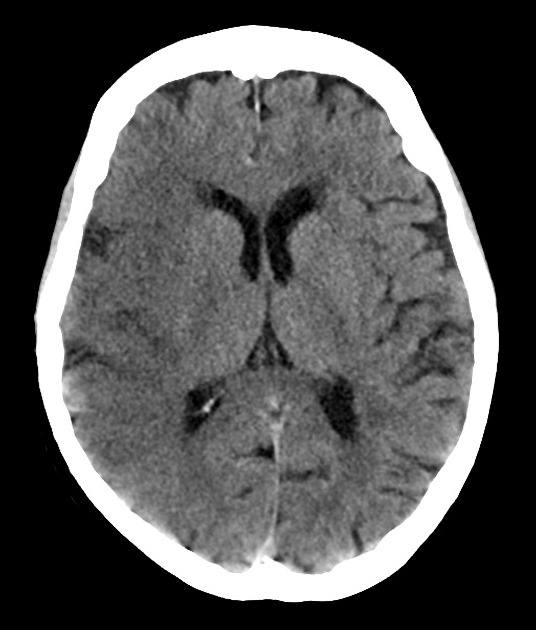

Nhồi máu não

» Thông tin: Nam giới – 60 tuổi.

» Lâm sàng: Đau đầu + Liệt nửa người trái / NIHSS 18 điểm.

# Nhồi máu sớm bán cầu phải thuộc vùng cấp máu ĐM não giữa / Huyết khối ĐM não giữa phải.